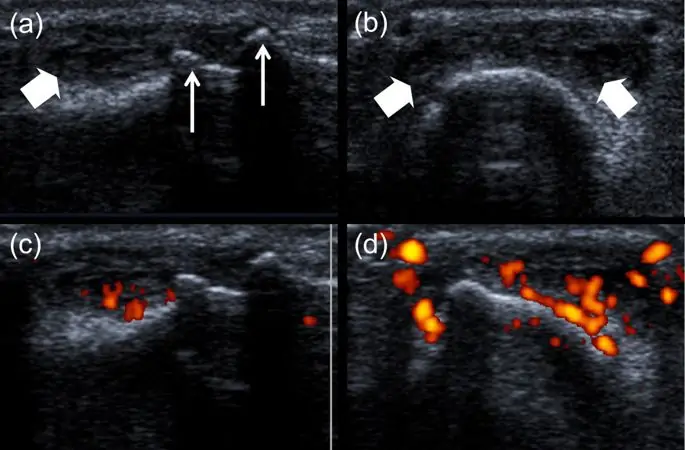

УЗИ позволяет визуализировать широкий спектр особенностей ОА кисти, включая остеофиты, краевые эрозии и синовит (рис. 2). Следовательно, УЗИ может быть реальным инструментом для визуализации воспаления у пациентов с ОА. Одним из недостатков УЗИ является неспособность его луча проникать в костную кору. Таким образом, из-за анатомии сустава визуализация суставного хряща и повреждения костей ограничивается в основном периферическими частями (29). Облегающие остеофиты, которые нарушают акустическое окно, еще больше усложняют оценку. В сильно поврежденных суставах может быть трудно определить точку, в которой начинается эрозия и заканчивается остеофит.

УЗИ 2-го проксимального межфалангового сустава. Сустав визуализируется в сагиттальном (a, c) и осевом (b, d) сканировании. На полутоновом изображении (а) видны проксимальный и дистальный остеофиты (стрелки). Сероватый синовит виден как в сагиттальной (а), так и в осевой (б) плоскостях (наконечники стрел). Сигнал энергетического допплера виден в (c) и (d).

Изображение в полном размере